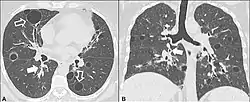

| CT scan of the lung showing bullae in the lower lung lobes of a subject with type alpha-1-antitrypsin deficiency. There is also increased lung density in areas with compression of lung tissue by the bullae. | |

A focal lung pneumatosis is an enclosed pocket of air or gas in the lung and includes blebs, bullae, pulmonary cysts, and lung cavities. Blebs and bullae can be classified by their wall thickness.[1]

- A bleb has a wall thickness of less than 1 mm.[2] By radiology definition, it is up to 1 cm in total size.[3] By pathology definition, it originates in the pleurae (rather than in the lung parenchyma).[4]

- A bulla has a wall thickness of less than 1 mm.[2] By radiology definition, it has a total size of greater than 1 cm.[3] By pathology definition, it originates in the lung parenchyma (rather than in the pleurae).[4]